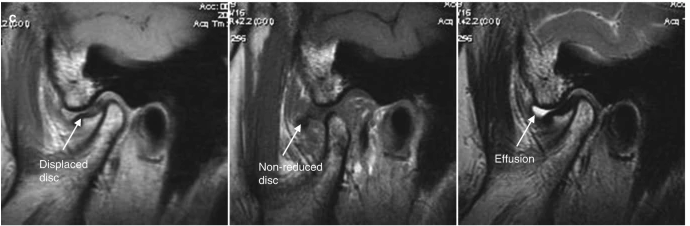

7

A